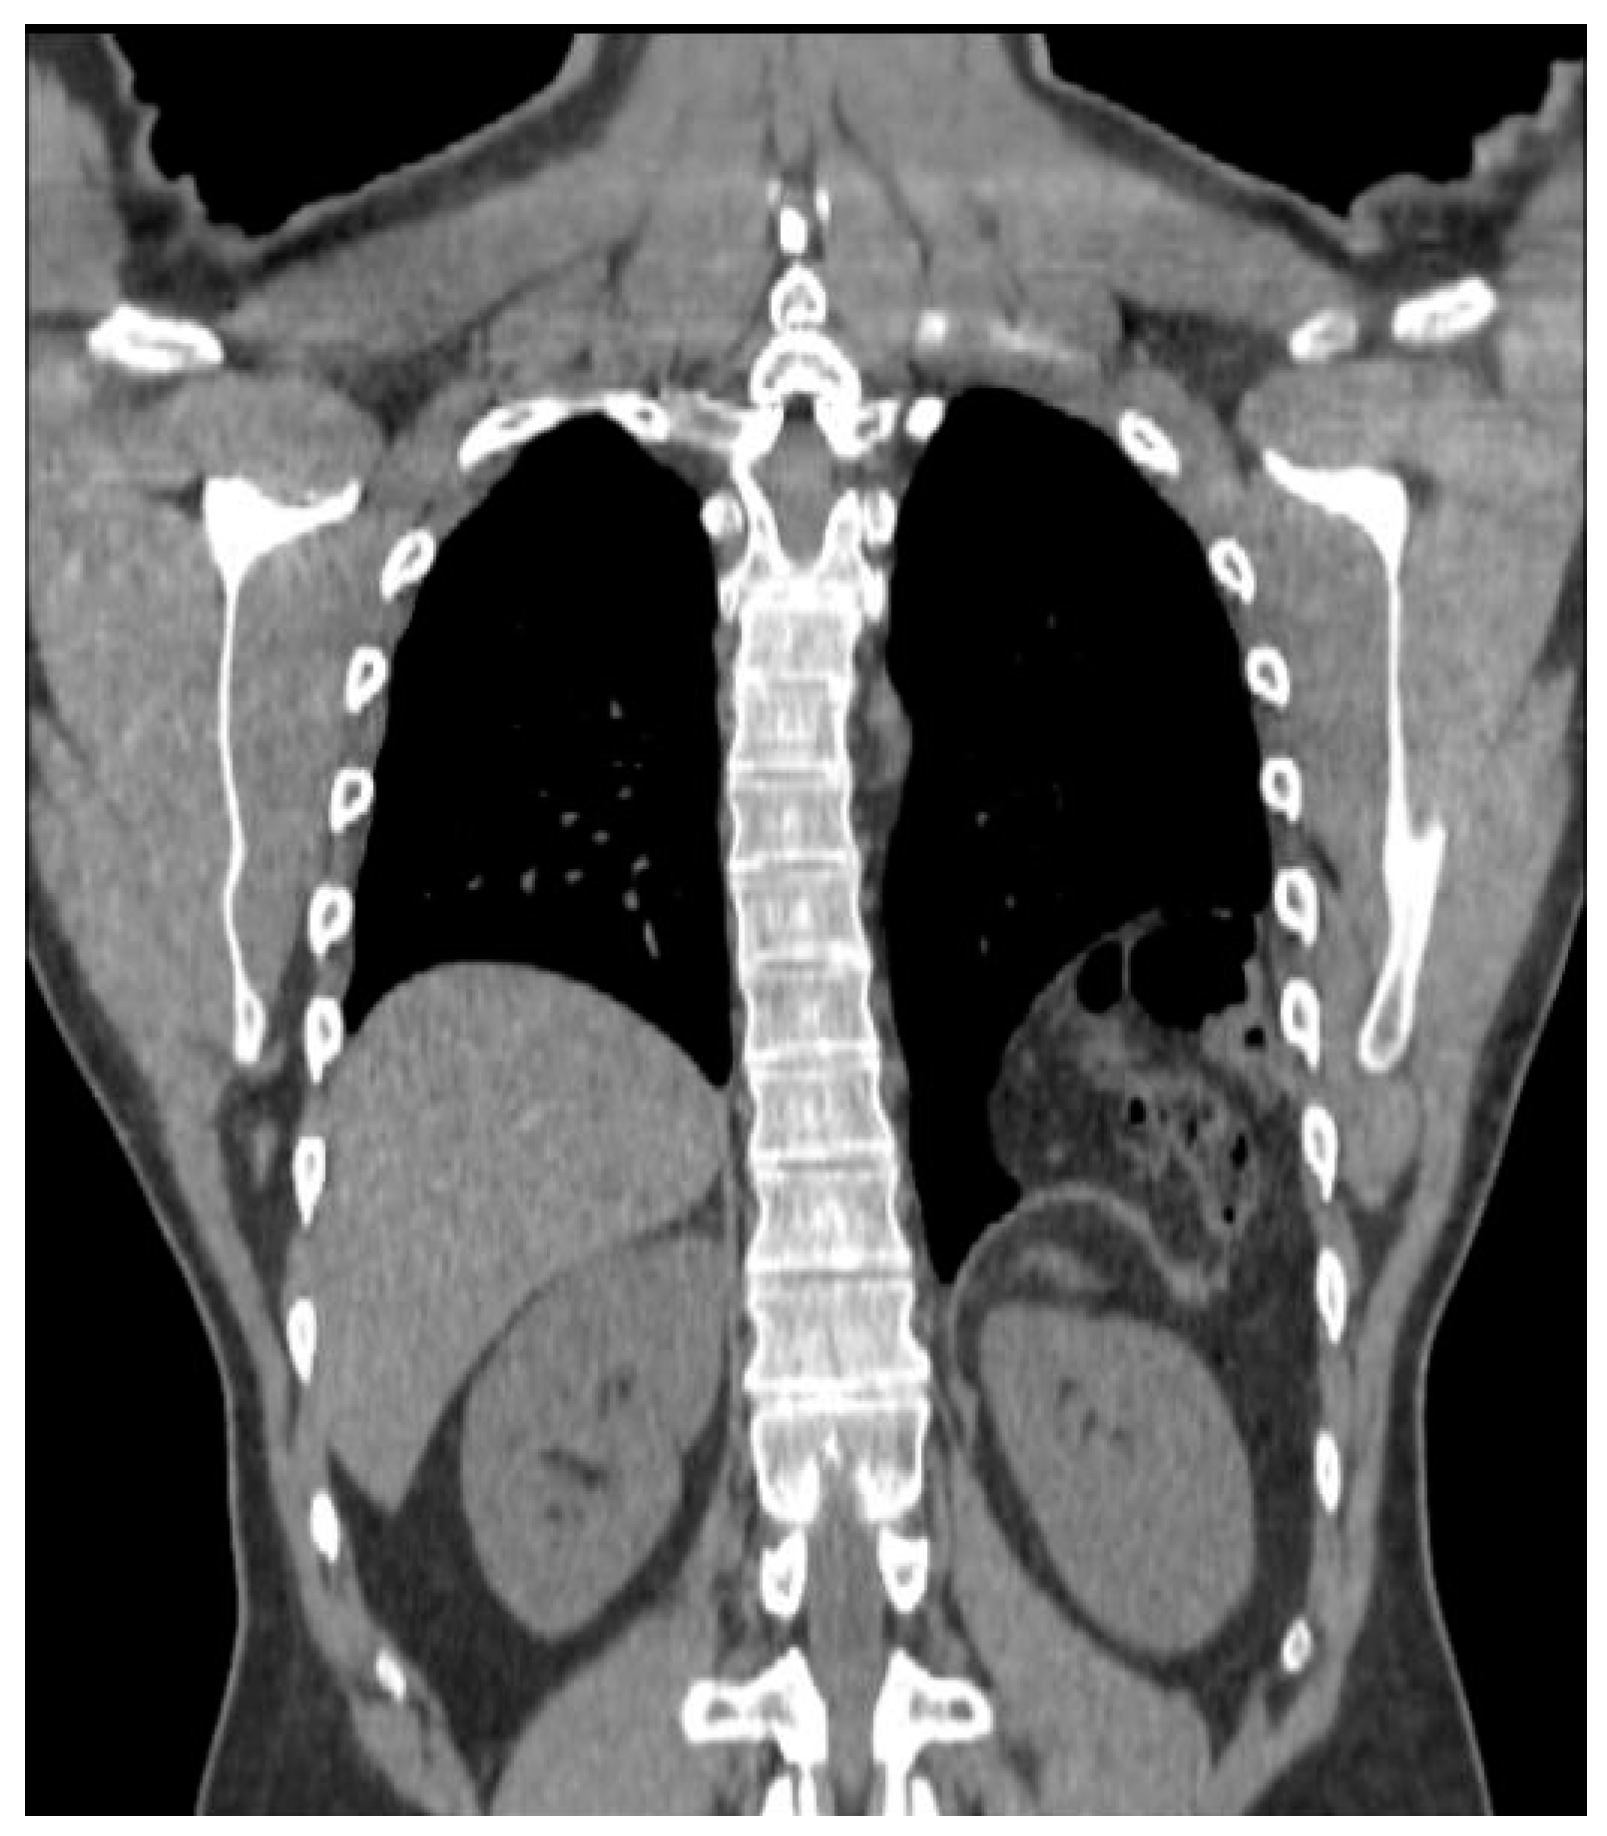

Between 2010 and 2018, the patient experienced increasing dyspnea on exertion and left chest discomfort. In February 2018, a CT showed the persistence of the hernia, which was measured as a 3.3 cm diaphragmatic orifice containing colon and greater omentum, for a total volume estimated at 560 cc (Figure 1 and Figure 2). He underwent preoperative consultation in June 2018, at which he complained of dyspnea, left chest discomfort, as well as occasional constipation. On clinical examination, the patient had scars from left subcostal and midline laparotomy incisions, as well as decreased left basilar breath sounds on chest auscultation.

Figure 1.

CT scan (performed in 2018) showing the recurrent left posterolateral hernia.